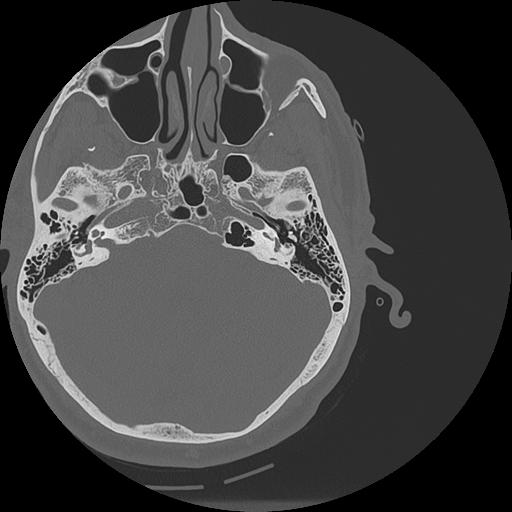

7 HUESO,,Vol,0.5,HUESO,,